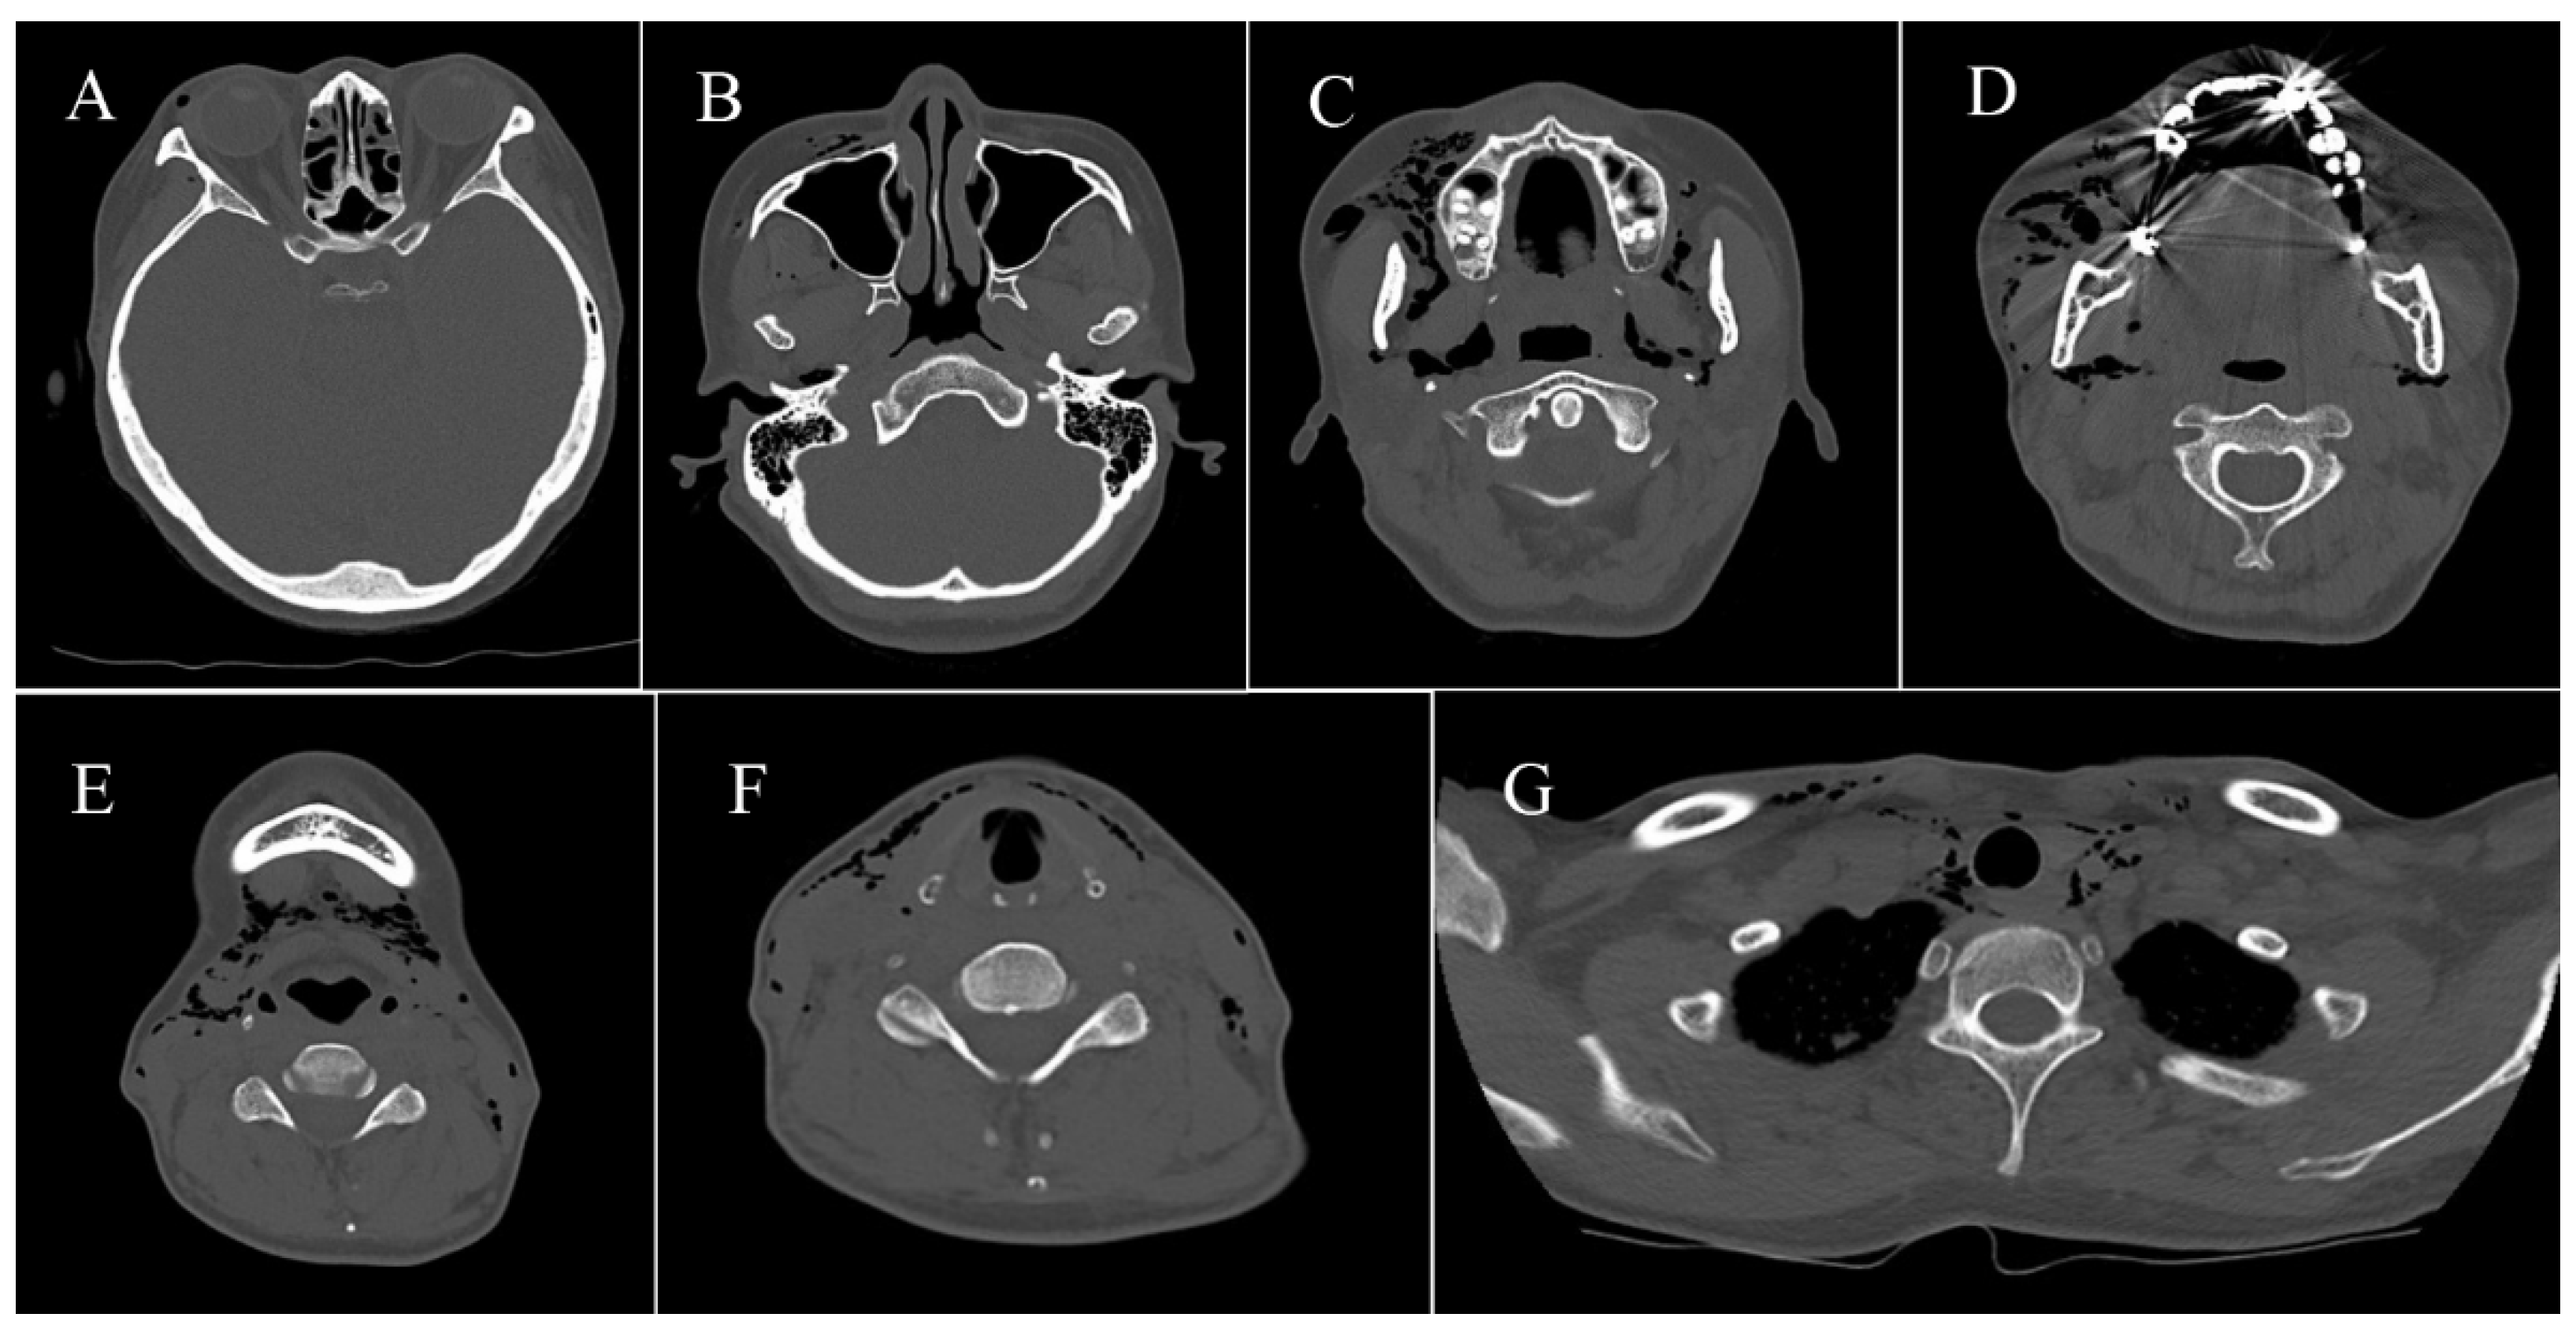

2.3.1. Case 1

2.3.2. Case 2

2.3.3. Case 3